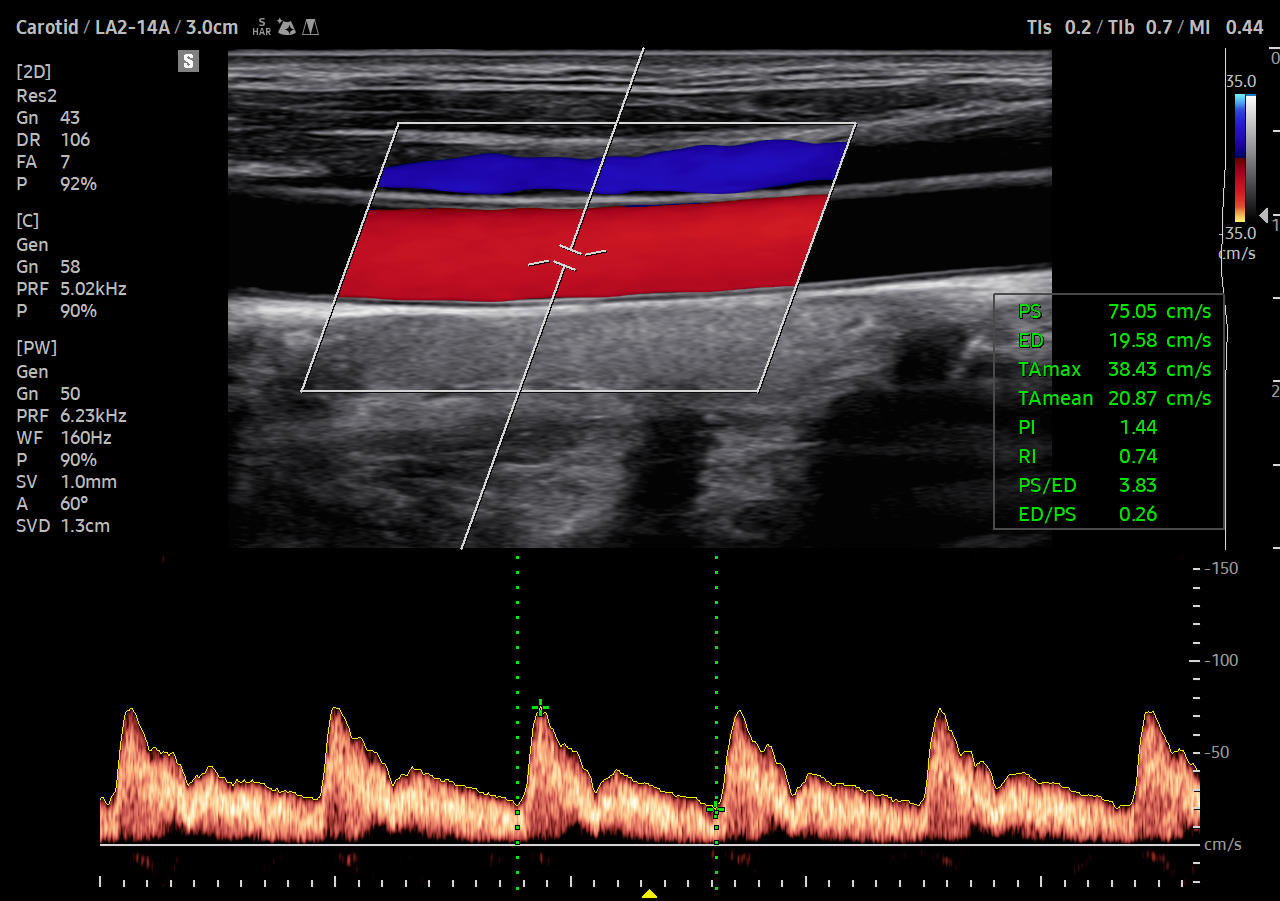

Detekce funkčních změn kardiovaskulárních cév

ArterialAnalysis™ zjišťuje funkční změny cév a poskytuje naměřené hodnoty, jako je tuhost, tloušťky intimy a medie a rychlost pulzní vlny krční tepny. Vzhledem k tomu, že k funkčním změnám dochází dříve než ke změnám morfologickým, podporuje tato technologie včasnou detekci kardiovaskulárních onemocnění.

![]()